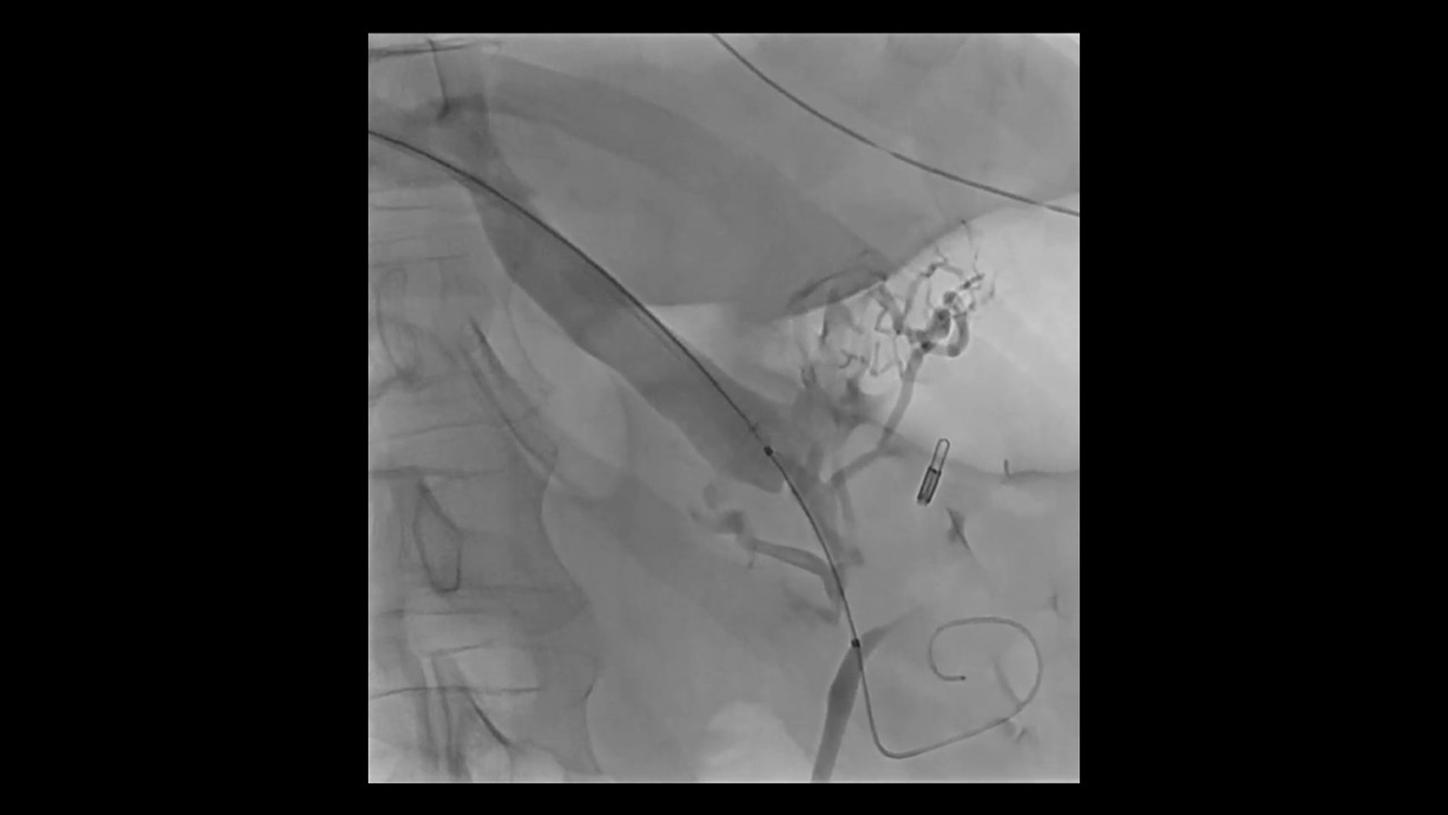

without OPTIQ AI

with OPTIQ AIOPTIQ AI delivers constant image quality* defined by CNR independent of C-arm angulation and patient size - in support of the ALARA10 principle throughout the procedure. And it optimizes device visibility based on the X-ray absorption properties of the respective material.

On top, an AI-powered algorithm reduces image noise in real time while better preserving structures11,12 across all 2D imaging modes and different body regions.